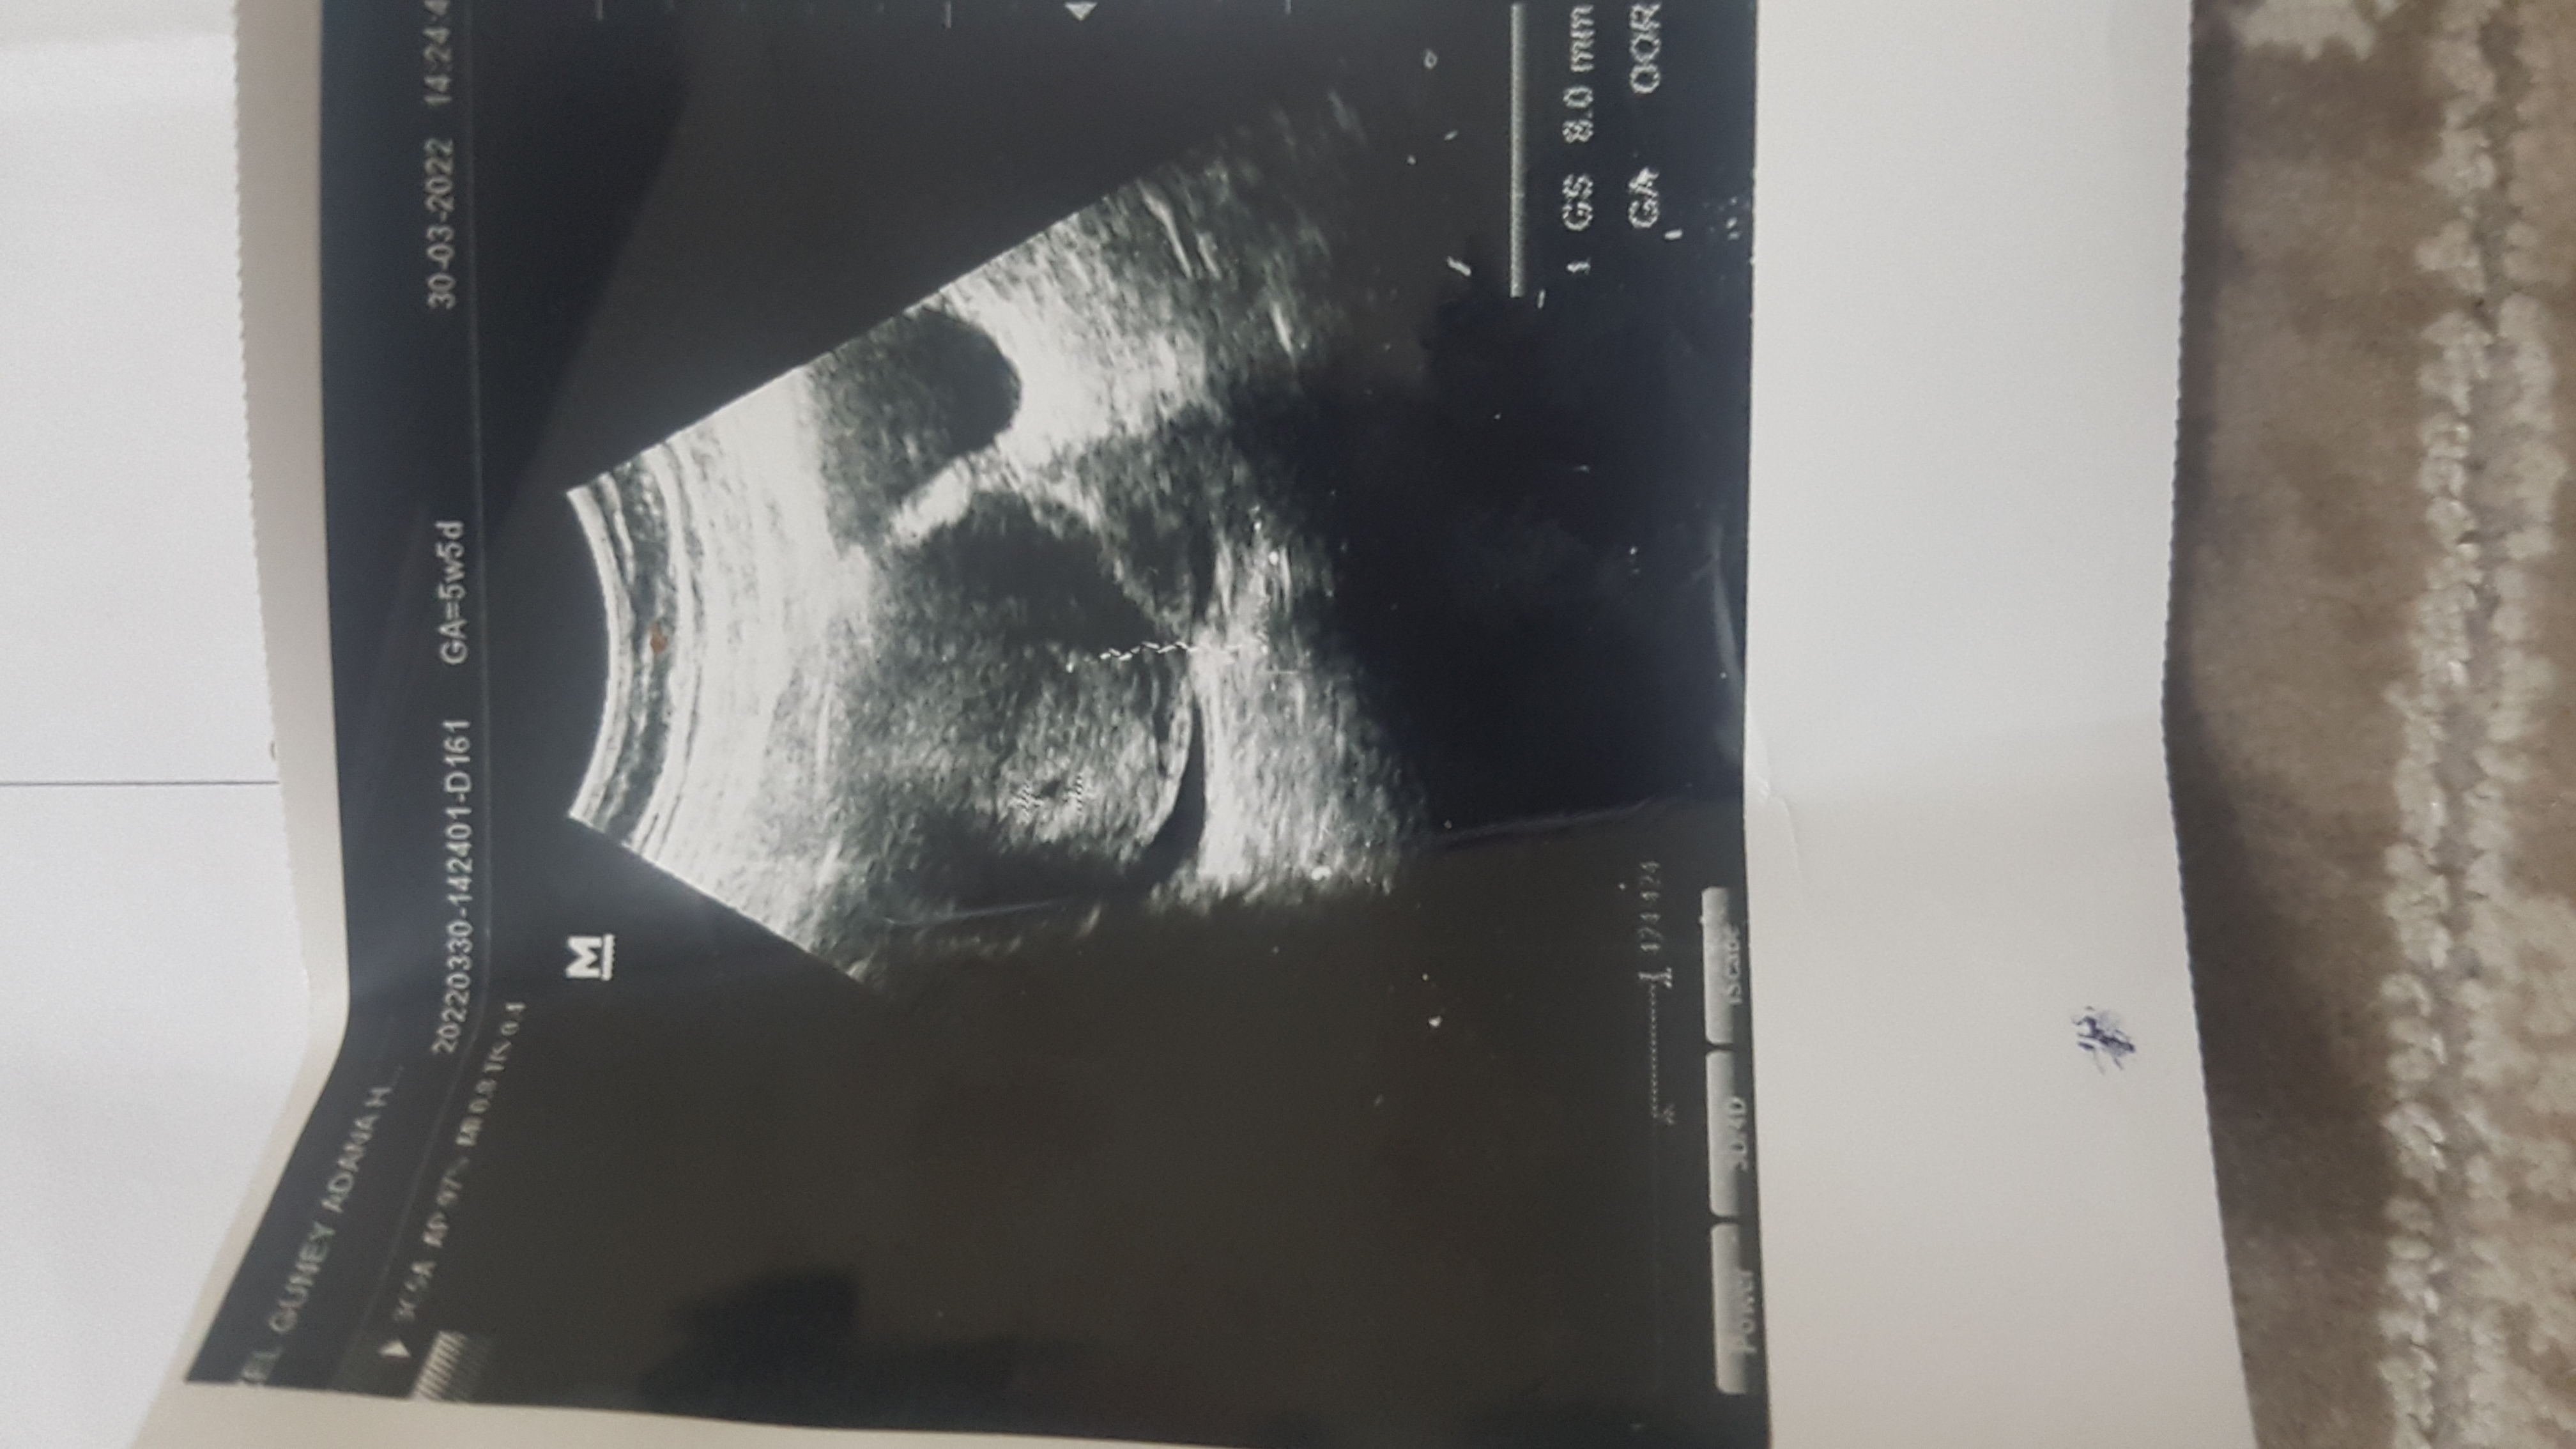

Kızlar selam ben yeni üye oldum 5 haftalık gebeyım sizce cinsiyeti ne 😊 2. Gebligim